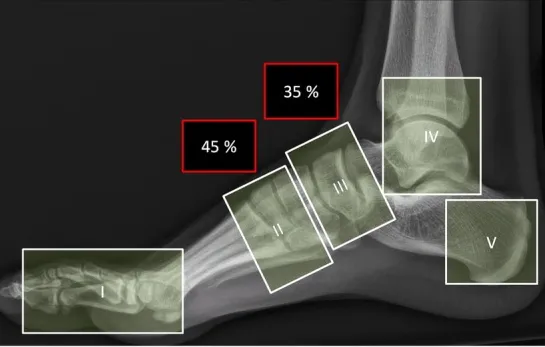

X-Ray